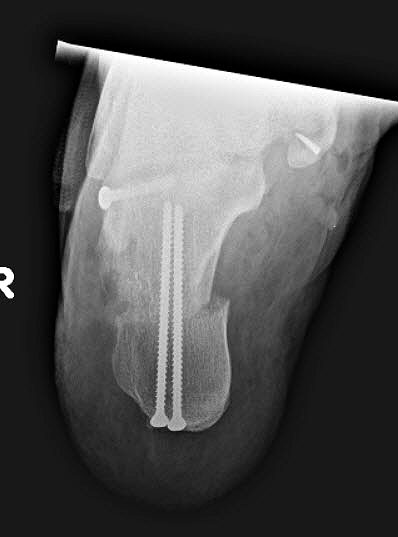

Radiologisches Beispiel einer fixierten Planovalgus Deformität Stadium III, 51 jähriger Patient. Stehendes präoperatives Röntgenbild und 1 Jahr postoperatives Röntgenbild des Fußes seitlich. Die Korrektur der Deformität umfaßte eine leicht korrigierende U

Abbildung 12

Im Stadium III der Tibialis posterior Sehneninsuffizienz bei fixierter Deformität und/oder erheblich eingeschränkter Inversion im USG aber stabilen und flexiblen Chopart-Gelenk und weniger als 10° fixierter Vorfußsupination eine in-situ oder leicht korrigierende USG-Arthrodese indiziert. Der Vorteil einer isolierten USG-Arthrodese gegenüber einer Triple- oder Double-Arthrodese ist die verbleibende, funktionell wichtige Beweglichkeit in der Chopart-Gelenkreihe. Um einem persistierenden fibulocalcanearem Impingement sicher vorzubeugen, sollte die USG-Arthrodese in maximal 5° Valgus- oder sogar Neutralposition erfolgen. Zur Prophylaxe eines Rezidivs wird die USG-Arthrodese zudem häufig mit einer medialisierende Tuber calcanei Osteotomie und / oder einem FDL-Transfer kombiniert (Abb. 12).